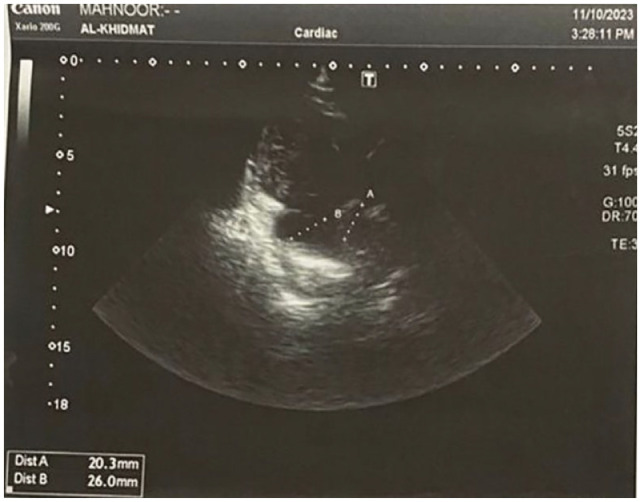

Case presentation: This case report discusses a 23-year-old female with Kartagener's syndrome, bronchiectasis, and cardiac involvement, who presented with shortness of breath, cough, and syncope. Notably, she received home oxygen therapy but became exhausted, leading to loss of consciousness. Clinical examination revealed prominent heart sounds and abnormal lung findings. Laboratory results indicated leukocytosis, and an ECG confirmed dextrocardia and cardiac abnormalities. Doppler studies identified mitral and tricuspid regurgitation along with severe pulmonary arterial hypertension. Antibiotics were administered for coagulase-negative Staphylococcus infection. The patient improved with a treatment regimen, including oxygenation and nebulization. Regular follow-up and patient education were emphasized.